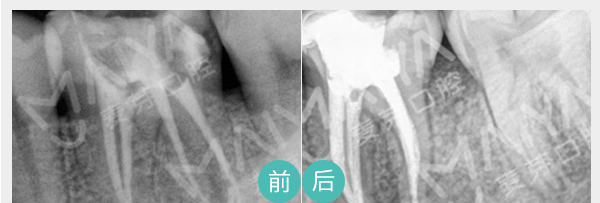

• 麦芽显微根管治疗

通过机械和化学方法去除根管内的大部分感染物,并通过充填根管、封闭冠部,防止发生根尖周病变或促进已经发生的根尖周病变的愈合。

适应症:牙髓炎、深度龋齿等